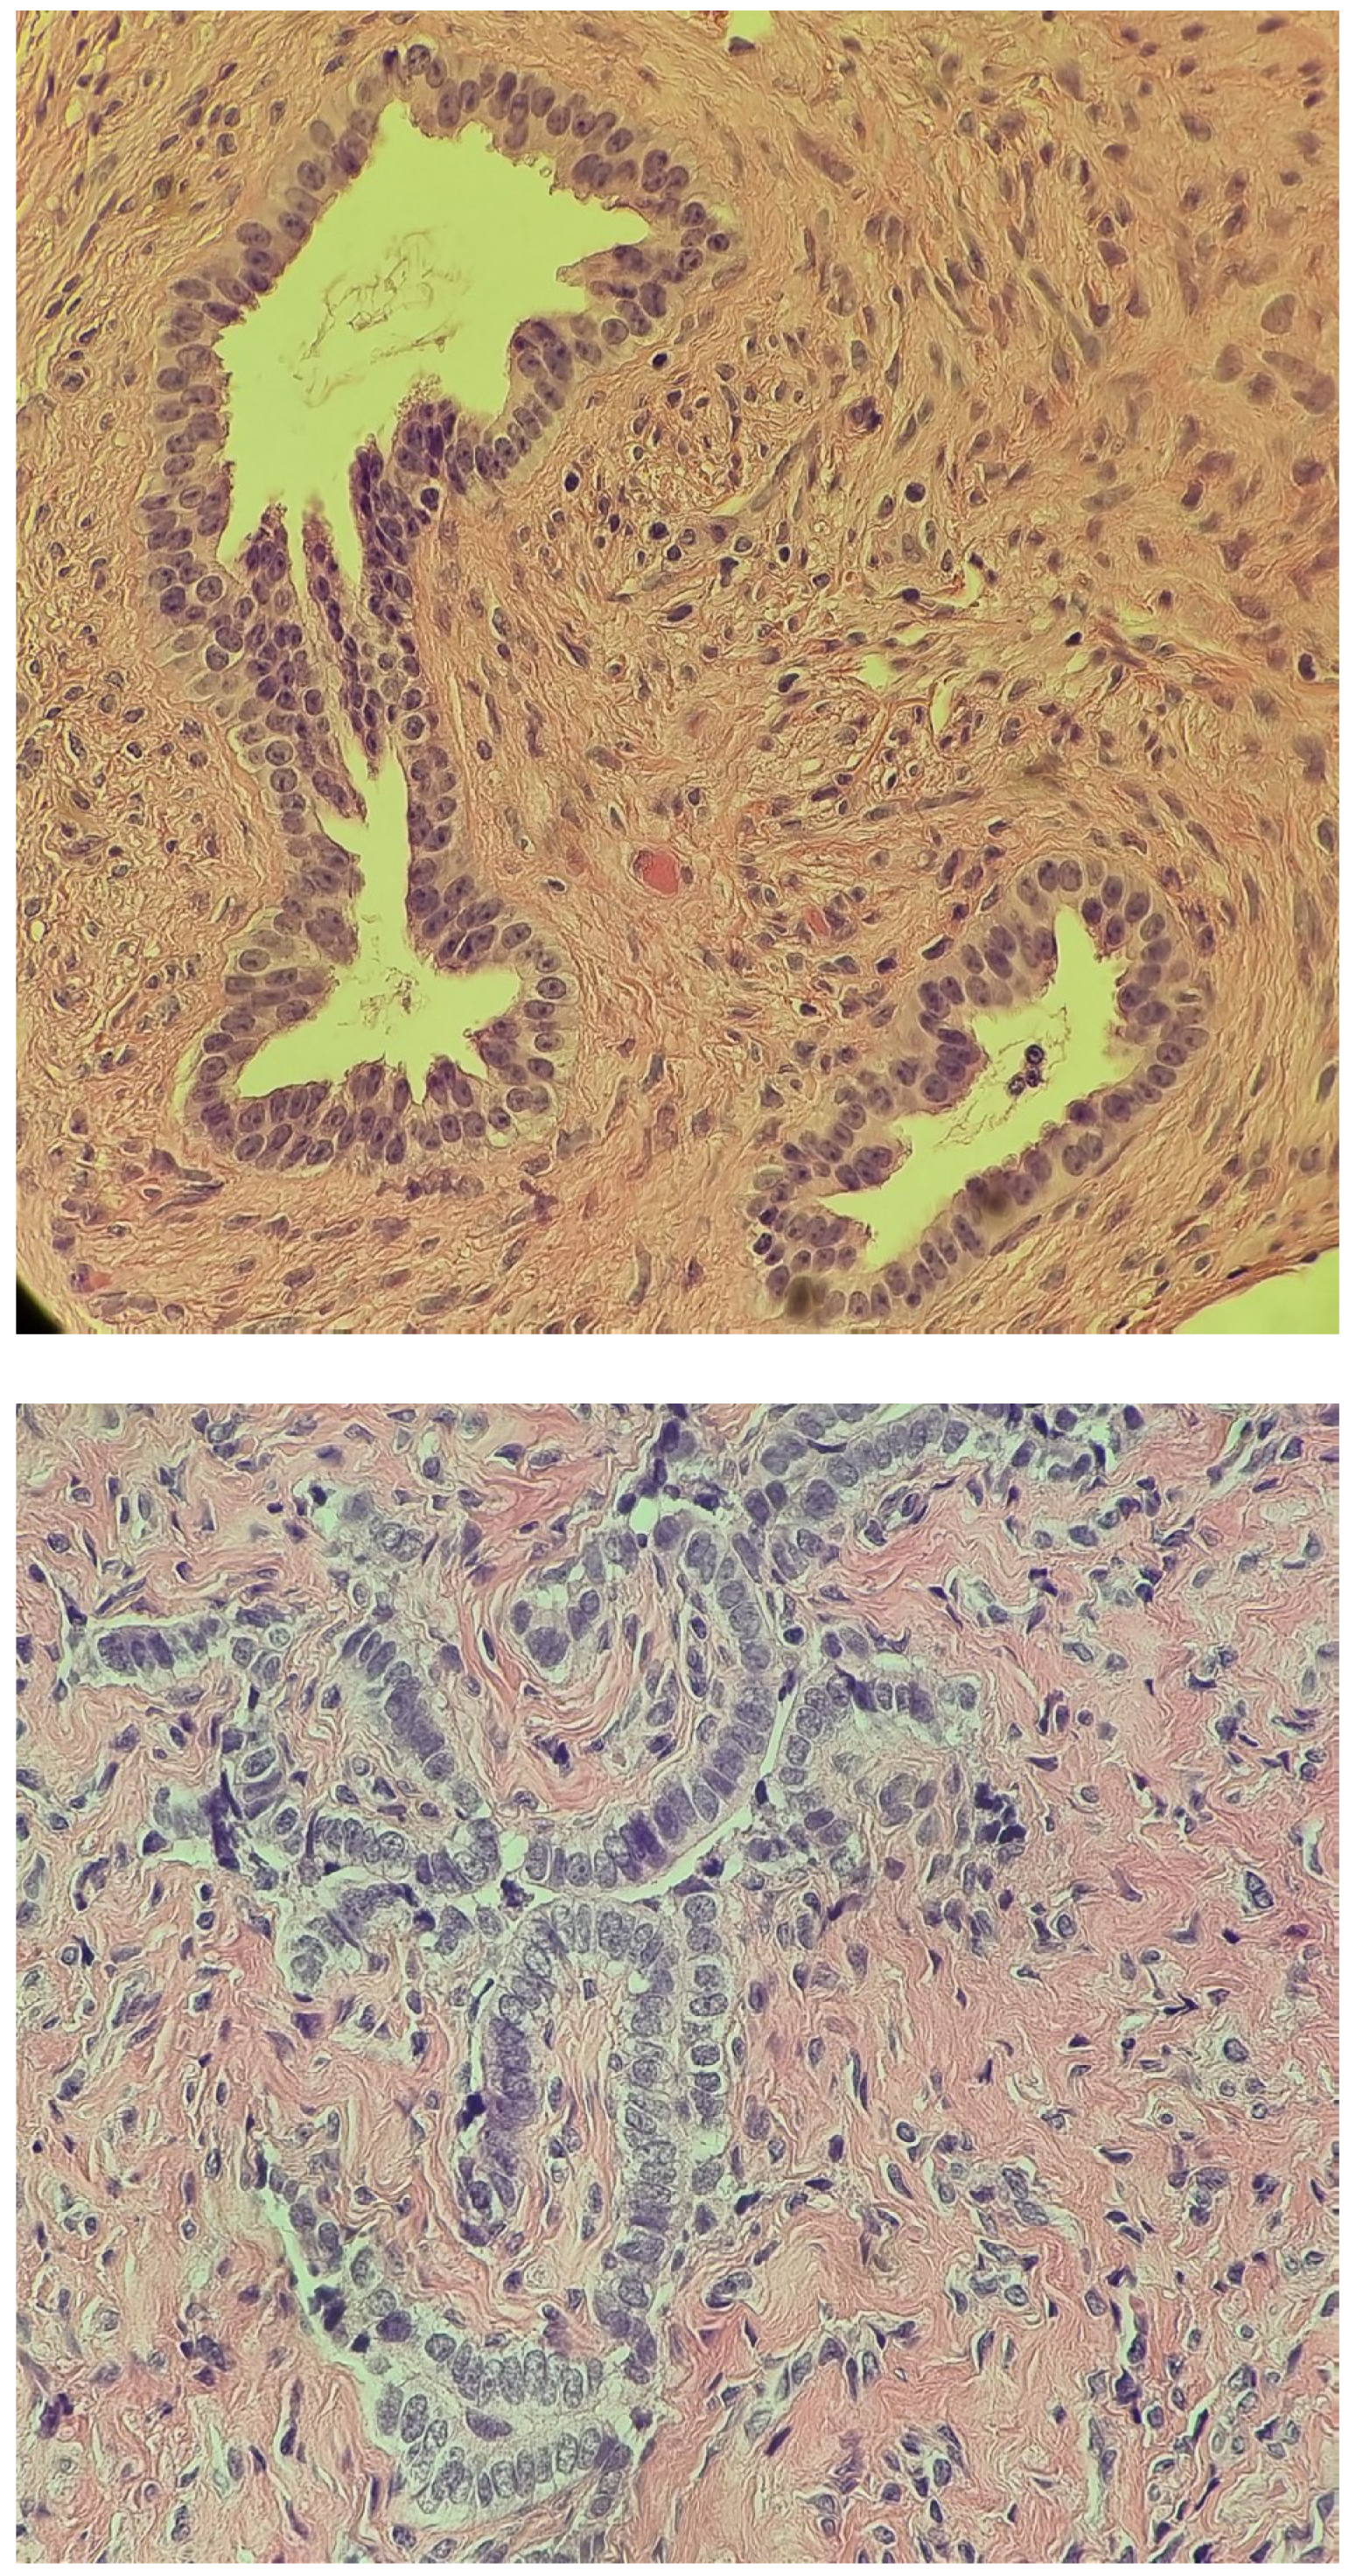

2.4. At Age 13 Years